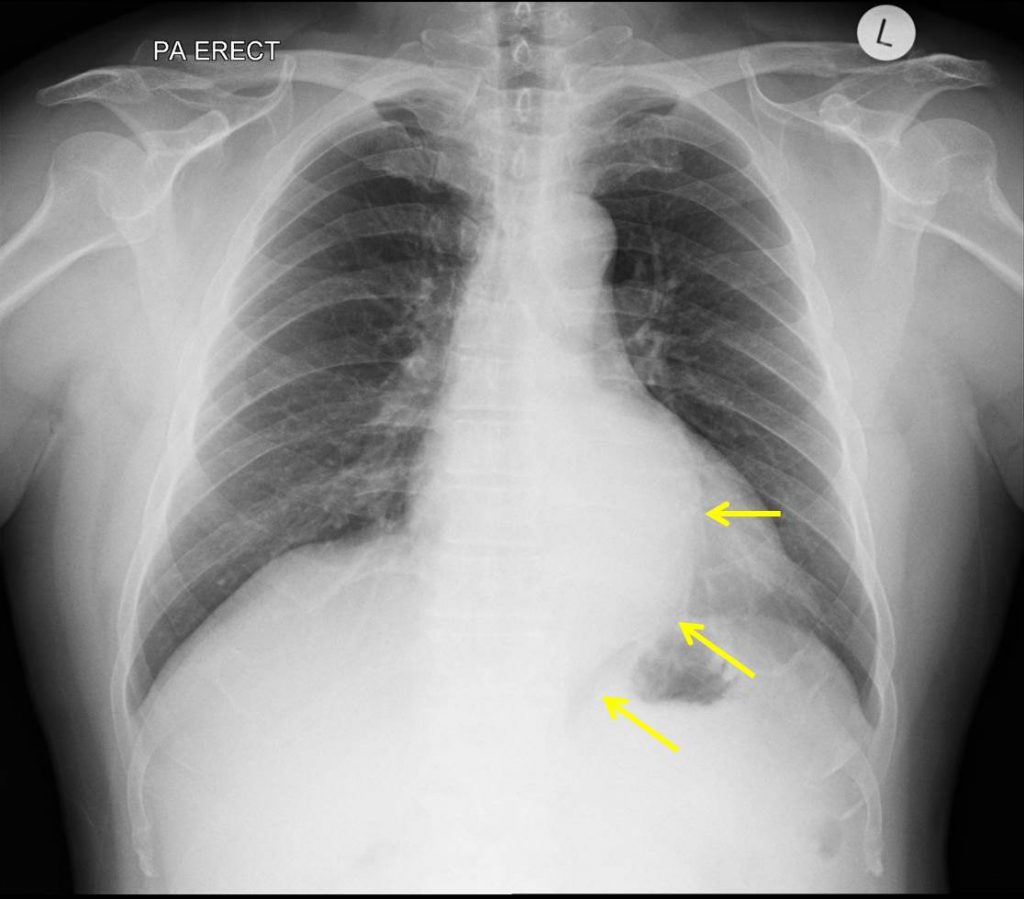

La tele de tórax es un tipo de radiografía en la que se utilizan rayos X para obtener imágenes detalladas de los órganos y tejidos dentro del tórax. Este examen se realiza con el paciente en posición erguida, generalmente de pie o sentado, para permitir una visión clara de los pulmones, el corazón, los vasos sanguíneos y las costillas. A veces, se puede realizar en posición acostada, dependiendo de la condición del paciente.

Se pueden realizar imágenes en diferentes vistas, como la posterior-anterior (PA), en la que el paciente se coloca con el pecho hacia el aparato de rayos X, y la lateral, en la que el paciente se coloca de lado. Durante el procedimiento, el paciente debe mantener una posición fija y seguir las indicaciones del técnico para evitar que las imágenes salgan borrosas. En ocasiones, se les pedirá que contengan la respiración por un breve momento para evitar que los movimientos respiratorios distorsionen la imagen.

6. Diafragma

El diafragma, que separa el tórax del abdomen, debe ser simétrico y no debe mostrar signos de hernias o desplazamientos que podrían ser indicativos de patologías como la hernia diafragmática.

La presencia de infiltrados en una tele de torax sugiere un proceso patológico que afecta el intersticio o los espacios alveolares del pulmón. Estos hallazgos radiológicos se manifiestan como áreas de mayor opacidad en la placa, indicando acumulación de líquido, células o material exudativo. La identificación y caracterización de estos infiltrados permiten orientar el diagnóstico y definir el manejo clínico adecuado.

La presencia de infiltrados en una tele de torax sugiere un proceso patológico que afecta el intersticio o los espacios alveolares del pulmón. Estos hallazgos radiológicos se manifiestan como áreas de mayor opacidad en la placa, indicando acumulación de líquido, células o material exudativo. La identificación y caracterización de estos infiltrados permiten orientar el diagnóstico y definir el manejo clínico adecuado. Uno de los principales motivos por los que se solicita una tele de tórax antes de una cirugía es la evaluación del estado pulmonar del paciente. Algunas condiciones respiratorias pueden afectar la capacidad de oxigenación y la recuperación postoperatoria, entre ellas: